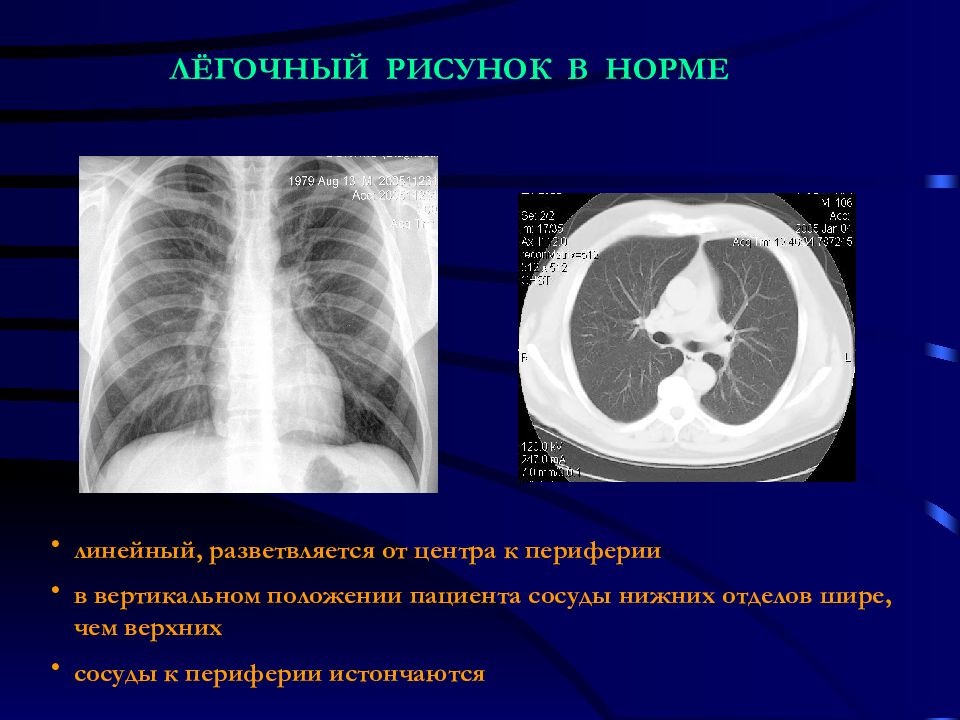

Фотографии, демонстрирующие обнаруженное усиление легочного рисунка

Раздел: Фотодневник открытий